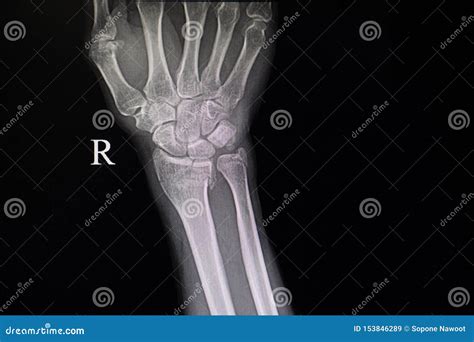

A broken hand, often diagnosed through an X-ray, involves a fracture in one or more of the bones in the hand. The hand is composed of 27 bones, including the metacarpals, phalanges, and carpals. Each of these bones can be susceptible to fractures, which can range from minor cracks to severe breaks.

• X-rays: X-rays are the primary imaging tool used to confirm the presence and type of fracture. They provide detailed images of the bones and can help determine the severity of the injury.

• Additional Imaging: In some cases, additional imaging tests such as CT scans or MRIs may be ordered to get a more detailed view of the fracture and surrounding tissues.